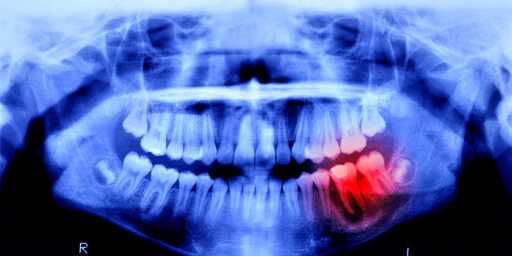

Teeth has got to be one of the most disrespected and undervalued parts of your body. Your body’s other bones can heal but then it’s like “fuck your teeth, I’m not doing shit about them”. And then we got health insurance companies who have the gall to not consider teeth an important part of your body that should be covered, got to get it separately and the costs are fundamental.

You can pretty much die from bad teeth, like rot and cavities. It is just a matter of when.

A tooth infection can easily spread to your brain and kill you. It’s a very short path.

doesnt need to spread to your brain, just cause sepsis lowering your blood pressure to dangerous levels, or to a major organ and kill you that way.